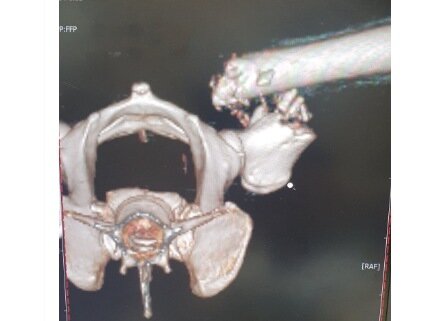

본문 이미지 - 골육종으로 부러진 다리 CT 사진(코난 아빠 제공) ⓒ 뉴스1

골육종으로 부러진 다리 CT 사진(코난 아빠 제공) ⓒ 뉴스1